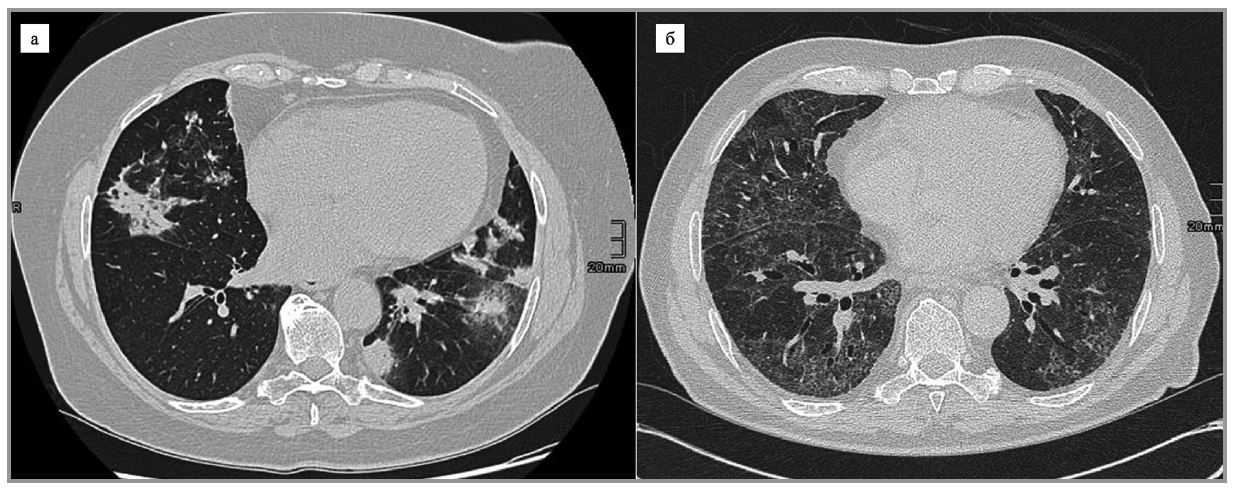

Л-ИЗЛ чаще всего проявляется как затемнения по типу «матового стекла» с консолидацией или без нее [8, 40, 51] и имеет базальное, периферическое и билатеральное распределение, часто затрагивая много долей [52]. Гетерогенность описания затрудняет установление истинной частоты каждого паттерна. Чаще всего встречаются изменения, напоминающие криптогенную организующуюся пневмонию (КОП) и неспецифическую интерстициальную пневмонию – НСИП (рис. 1), реже – гиперчувствительный пневмонит (ГП)-подобные изменения [11, 20, 50, 52].

Рис. 1. МСКТ-паттерны Л-ИЗЛ: а – КОП; б – НСИП.

Паттерн НСИП чаще встречается у пациентов с Л-ИЗЛ, вызванным химиотерапией [9]. Ретикулярные изменения и уменьшение объема легких выявляются реже [36]. В современной классификации это соответствует фиброзирующей НСИП или обычной интерстициальной пневмонии [3]. Реже обнаруживаются внутригрудная лимфаденопатия и плевральный выпот [53]. Проявления, напоминающие саркоидоз, описаны при лечении интерфероном α [11]. Также при Л-ИЗЛ может встречаться другой паттерн затемнения по типу «матового стекла» с утолщением междольковых перегородок (симптом «сумасшедшей исчерченности»), имеющий низкие чувствительность и специфичность [53].